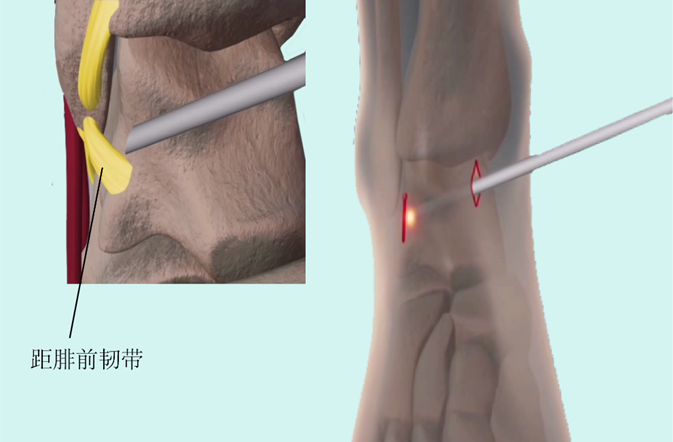

▶关节镜下微创术

① 韧带修复术(Brostrom术);

② 韧带加强术。

图18:关节镜下距腓前韧带探查修复术